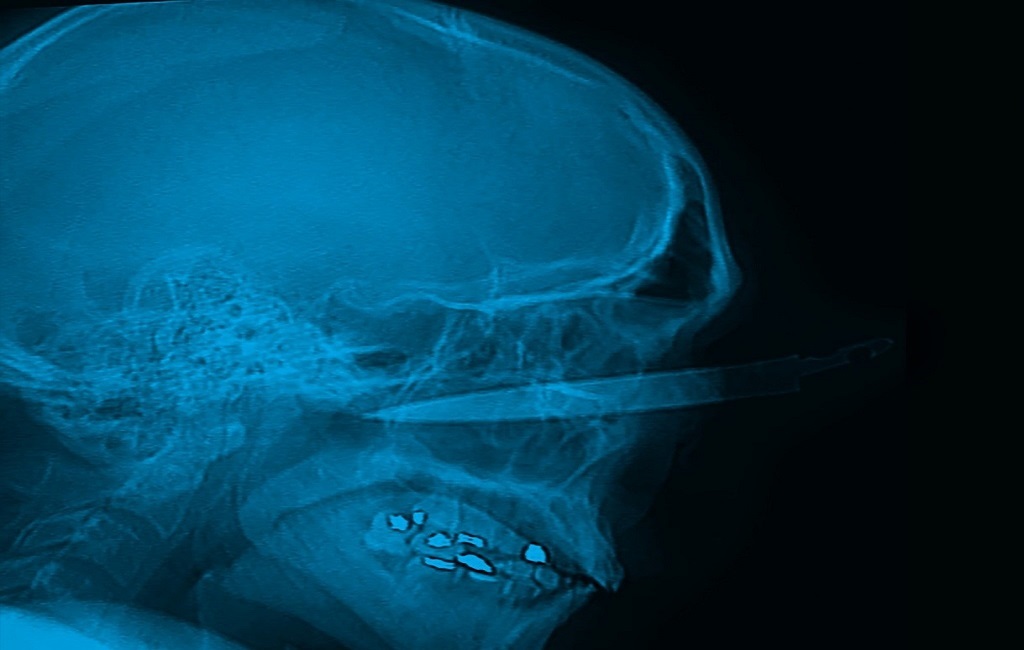

En sorprendente cirugía, médicos del hospital El Tunal retiran cuchillo del ojo de un hombre

Un exitoso procedimiento realizado por médicos del hospital El Tunal permitió salvarle la vida a un hombre de 35 años que, en medio de una discusión familiar, recibió una grave herida de arma cortopunzante en su ojo izquierdo.

“El paciente ingresó a los servicios de urgencias de este hospital con un cuchillo de, aproximadamente, 20 centímetros de longitud en su ojo izquierdo, atravesando el globo ocular, lo que puso en riesgo su vida. Los médicos procedieron a estabilizarlo y luego pasó a cirugía”, afirmó Germán Portocarrero Riascos, médico hospitalario de la Subred Sur.

La gravedad del paciente movilizó a los equipos de imagenología, urgencias, cirugía neurológica, cirugía maxilofacial y oftalmología, a trabajar coordinadamente para evitar el máximo de secuelas y retirarle el cuchillo que atravesaba el ojo, en dirección hacia su cerebro.

Tras una cirugía de varias horas, que buscó descartar y evitar compromisos neurológicos, se retiró lentamente el objeto cortopunzante, dejando al descubierto traumas en los huesos faciales ocasionados por el arma.